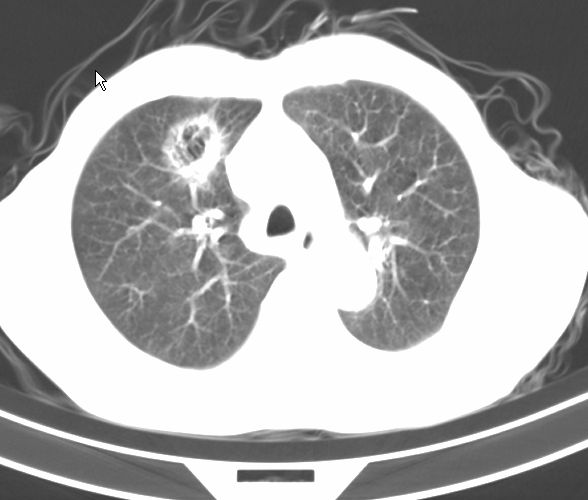

请大家看看是什么性质的。炎性病变首先考虑哪一种炎症。

炎性病变,金葡?建议痰检!

支持右肺上叶前段\\下叶内基底段感染,建议抗炎治疗后复查,除外结核.

支持右肺上叶前段、下叶内基底段感染,建议抗炎治疗后复查,除外结核.

右肺上叶前段及下叶内基底段感染性病变;建议抗炎治疗后复查。

楼主说是炎症,凭啥?典型的周围型肺癌(腺癌可能性大),肝内可能已有转移,强化看看吧。